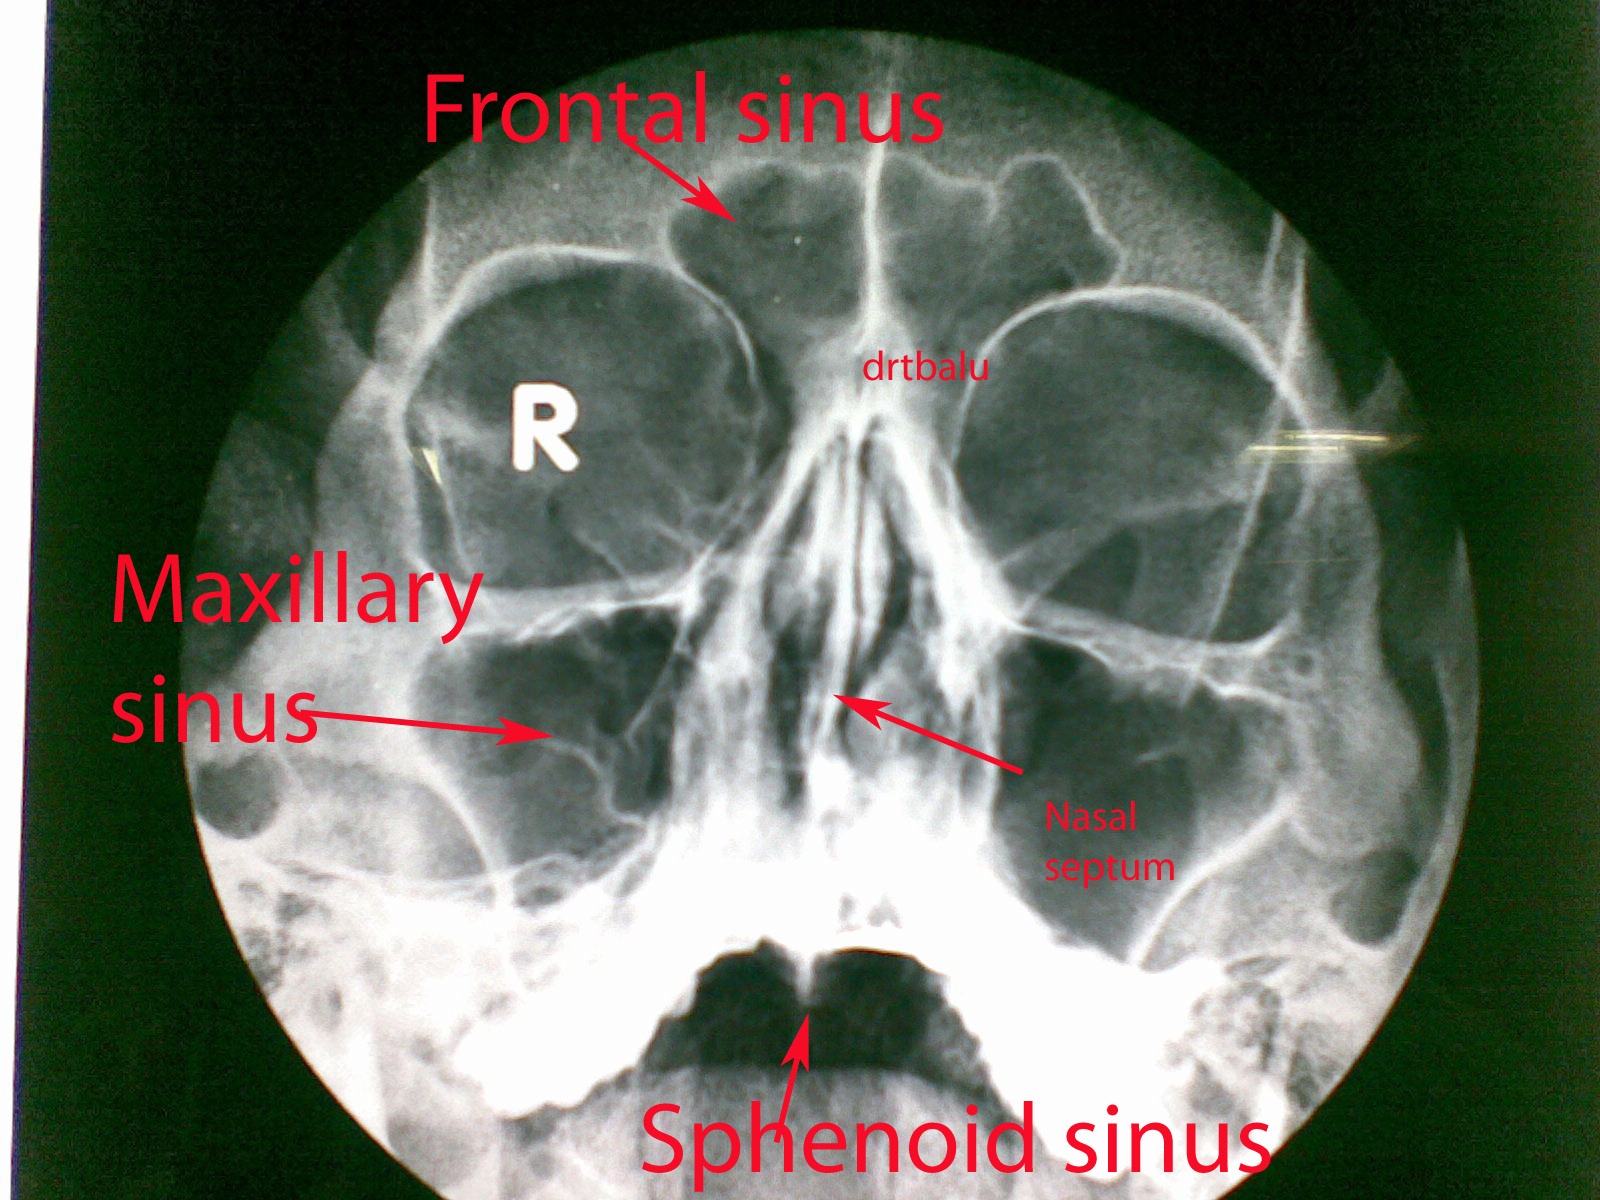

Role of X-rays in Otolaryngology

Even with the advent of modern imaging modalities like CT scan, MRI and PET scan, I personally feel that x-rays still have a role to play in diagnosing otolaryngological ailments. Radiograph is the most underestimated tool in the diagnostic armamentorium.